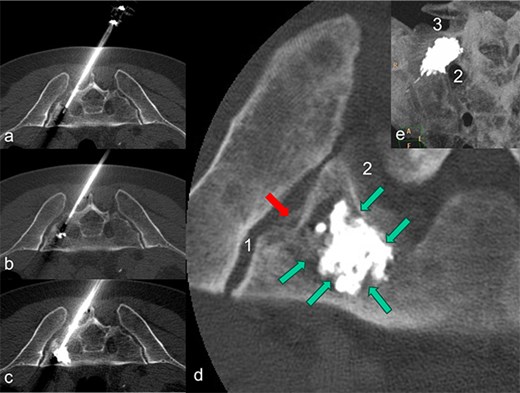

After discussing the treatment options and outcomes with the patient, we opted for the latest technique involving radiofrequency-activated ultrahigh-viscosity cement. The procedure was performed under intubation anesthesia with continuous anesthesiological monitoring. The patient was positioned prone in the CT scanner, and as part of routine practice, a single-shot antibiotic (cefazoline 2 g i.v.) was administered during the procedure. Based on the available access routes [11], the short axis of the sacrum was selected as the optimal entry point. Using a Jamshidi needle, access to the fracture zones was achieved dorsally. The cavity in the sacrum was filled with radiofrequency-activated bone cement (polymethylmethacrylate, PMMA; ER2 Bone Cement, DFine Europe) through the StabiliT Vertebral Augmentation System (DFine Europe) (Fig. 2a and b). The defect area was filled in a controlled, stepwise manner using single-slice CT guidance (Fig. 3a–c), with a total of 7 ml of PMMA cement.

The patient is lying prone in the CT. The needle of the application system (a) was inserted from the dorsal side via the short axis. During the cement insertion, the successive, discontinuous filling of the metastasis-related defect zone in the right lateral mass of the sacrum is shown in (a) to (b). The highly viscous cement activated by radio frequency enables precise augmentation while simultaneously blocking a leak. In (d), the inserted PMMA cement is placed centrally in the defect zone as a cement seal (marked by green arrows); there is no cement leakage through the pathological fracture (marked by a red arrow) in the direction of the sacroiliac artery (1) and the neuroforamen (2). A MIP-reformation (d) shows the cement filling, whereby here too there is no leakage in the direction of the neuroforamen (2) and the adjacent disc space (3).

Final imaging with low-dose, thin-slice spiral CT (Philips Brilliance TM CT 16-slice Big Bore, Philips GmbH DACH Healthcare, Hamburg, Germany) showed a well-centered cement distribution without leakage into the neural foramina, sacroiliac joint, adjacent disc space, or visceral surface of the sacrum (Fig. 3d and e). Post-procedurally, the patient experienced a reduction in pain to a VAS score of 4. His mobility, previously limited by pain, improved significantly, allowing for discharge 2 days after the procedure. By the time radiation therapy commenced, ~2 weeks after the RFS, the patient’s back pain had decreased to a VAS score of 2, and he was able to walk unaided. Any intermittent pain in the pelvic bones and spine was managed with NSAIDs at that time.